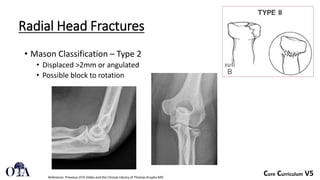

Fracture Management for Primary Care Physicians - ppt download